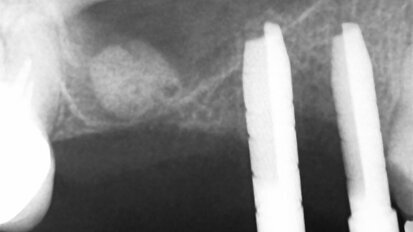

Zóny na CBCT čelisti

Kvalita kosti vztahující se k umístění implantátu